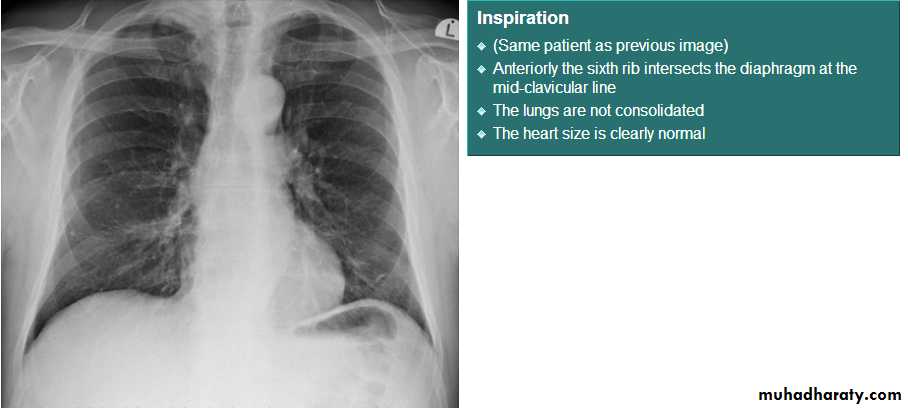

Both should exposed in full insp. And patient in upright position.Films taken in exp. Are difficult to interpret because:

• 1- hazy lung base.

• 2- heart shadow increase in size.

On good insp., the dome of rt. Hemidiaphragm at level of ant. End of 6th rib.

The rt. Hemidiaphragm being up to 2.5 cm higher than the left.

8- assess technical quality of the film: correctly exposed routine PA CXR is one in which the ribs and spine behind the heart can be identified but lung not overexposed.straight film is one where the medial ends of clavicles are equidistant from thoracic verteb.